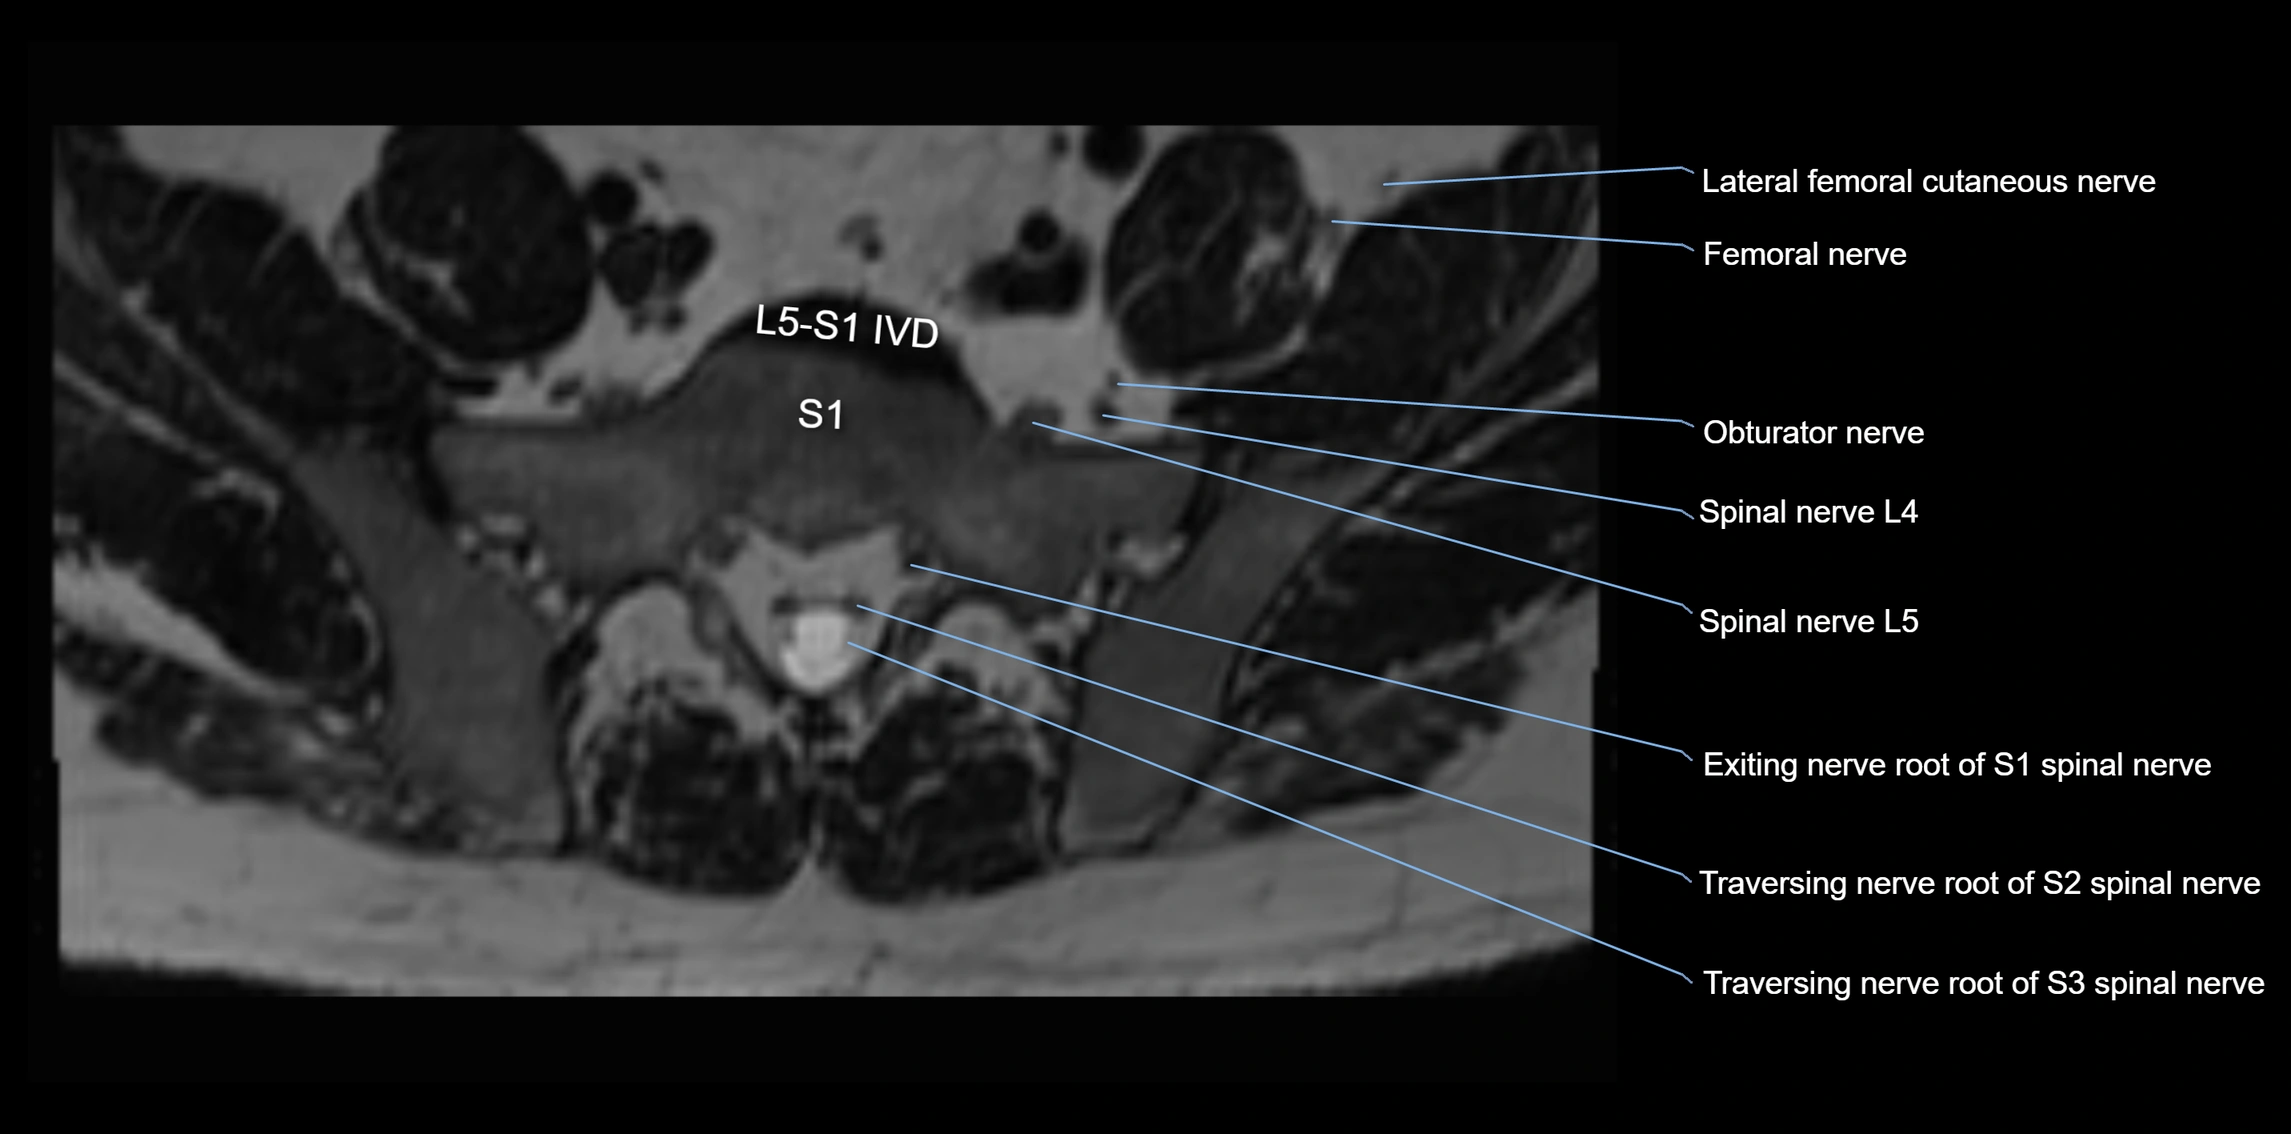

MRI Appearance

T1-weighted images:

• Nerve appears as a very thin low-to-intermediate signal intensity structure

• Surrounded by bright fat, aiding visualization

T2-weighted images:

• Nerve shows intermediate to mildly hyperintense signal compared to muscle

• Pathological involvement appears brighter

STIR (Short Tau Inversion Recovery):

• Normal nerve appears dark

• Inflamed or entrapped nerve appears bright hyperintense

T1 Fat-Sat Post-Contrast:

• Normal nerve enhances minimally

• Pathologic nerve (neuritis, entrapment, tumor infiltration) shows focal or diffuse enhancement

3D T2 SPACE / CISS:

• Nerve appears intermediate to mildly hyperintense compared to muscle

• Surrounded by bright fat or CSF, improving visualization

• Best sequence for mapping small pelvic nerves such as the anococcygeal